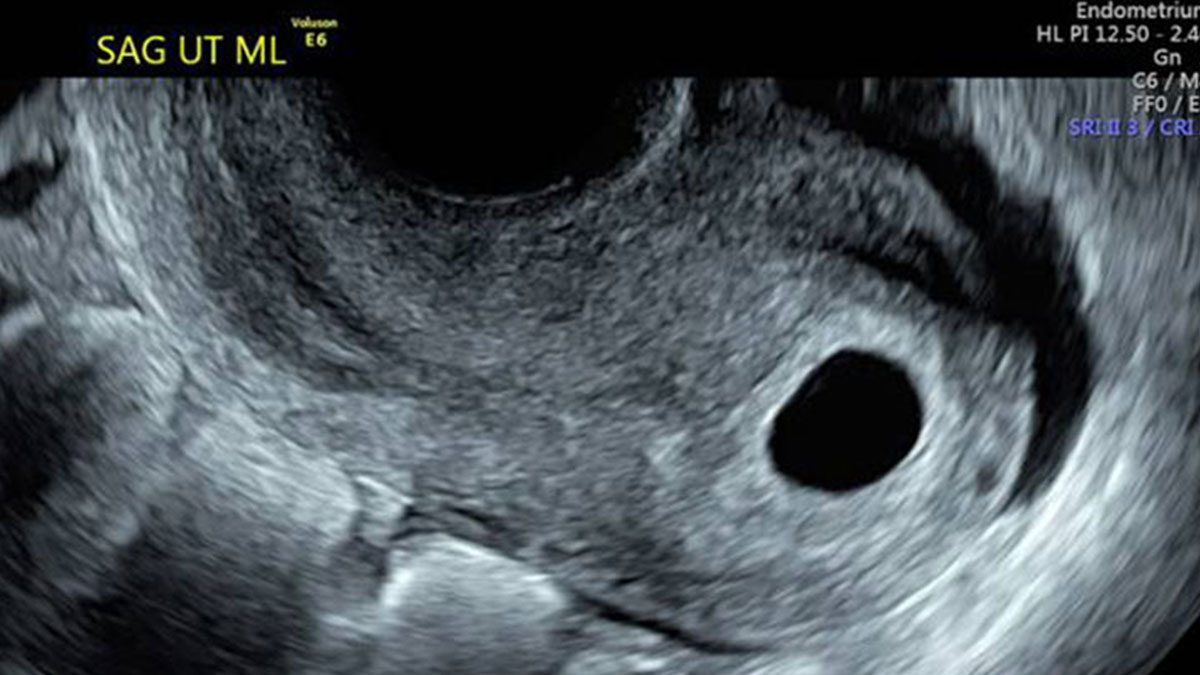

Boş gebelik transvajinal ultrason ile kolayca teşhis edilebilir. Bu muayene genellikle gebeliğin 7 ila 9. haftasında gerçekleşir. Zira bu haftalarda embriyo net bir şekilde görülmelidir. Eğer boş gebelik söz konusuysa, kese içi boş bir baloncuk gibi görünür. Bununla birlikte doktor tanıyı doğrulamak için bazı kan testleri de yapmak isteyebilir.